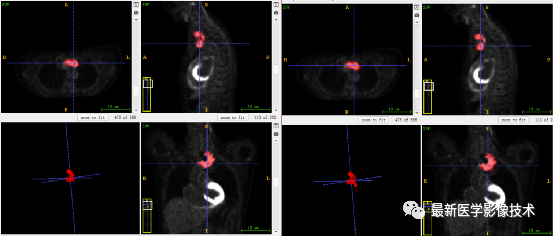

7、验证集分割结果:输入整个图像通过滑窗叠加预测结果,左图是金标准,右图是预测结果